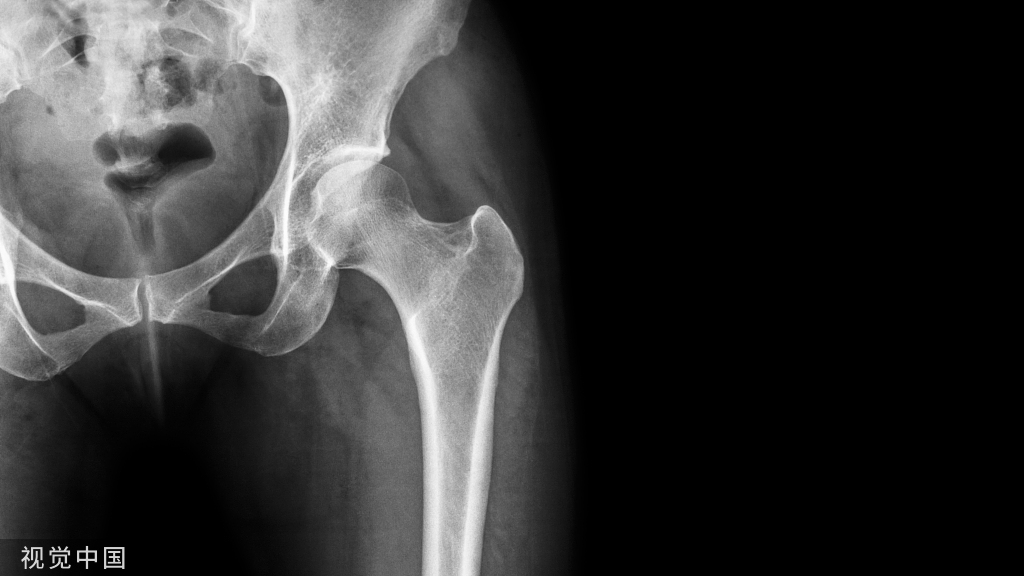

目前我国已经进入老龄化社会,这是不争的事实。同时伴随医学的快速发展和科技的飞速进步,原来一些无法治疗的老年患者骨关节病变,现在能够得到很好的医治,尤其是行人工关节置换术,能取得理想的治疗效果。然而,在这过程中也呈现一些新的棘手的医学问题(比如 :骨水泥反应综合征),而对老年患者手术期间的安危造成极大的影响。所谓骨水泥反应综合征,是指围术期应用骨水泥植入人体内以后所产生的以低血压、心律失常、弥漫性肺微血管栓塞、休克,甚至心搏骤停、死亡为临床表现的一种综合征。

(1)社会老龄化的到来,人体随着年龄的增加,身体的各个器官和系统功能逐渐下降,而这其中以骨质疏松和骨关节病最为突出。前者表现为骨质脆性增加,在受到外力作用下极易发生骨折 ;后者则主要表现为慢性关节疼痛,关节功能障碍和丧失。这些病变均严重影响老年人晚年身体健康和生活质量。随着经济水平的提高,接受人工关节置换的高龄患者越来越多,对绝大多数老年患者都能取得良好效果,故这种手术治疗方式已在临床广泛推广。因此,人工关节置换术在老龄化社会中的客观需求性将会显得愈来愈突出。

(2)老年患者人工关节置换术时骨水泥反应综合征的发生情况 :由于高龄患者多数存在骨质疏松,在人工关节置换手术中经常需要用到骨水泥( bone cement)。目前常用的生物骨水泥分为生物相容性较差的PMMA 骨水泥和生物相容性较好的磷酸钙骨水泥。随着骨水泥的广泛应用,骨水泥对心血管的影响,以及由此产生的“骨水泥反应综合征”在手术期间时有发生。Woo等综合文献报道后发现,骨水泥综合征导致心搏骤停的发生率为0.6% ~10%,病死率为0.02% ~0.5%。目前,无论手术医师,还是麻醉医师,均对老年患者人工关节置换术时骨水泥反应综合征的发生高度警惕。